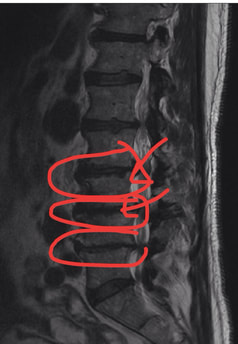

In some people this degenerative process is not associated with pain, while in others degenerative disc disease can cause neck and back pain, stiffness, and soreness. Degenerative discs can rupture, leading to arm or leg pain if the disc pinches nerves. The process of degeneration causes discs to gradually lose height, form spurs, and cause narrowing around the nerves, which can also lead to arm and leg pain